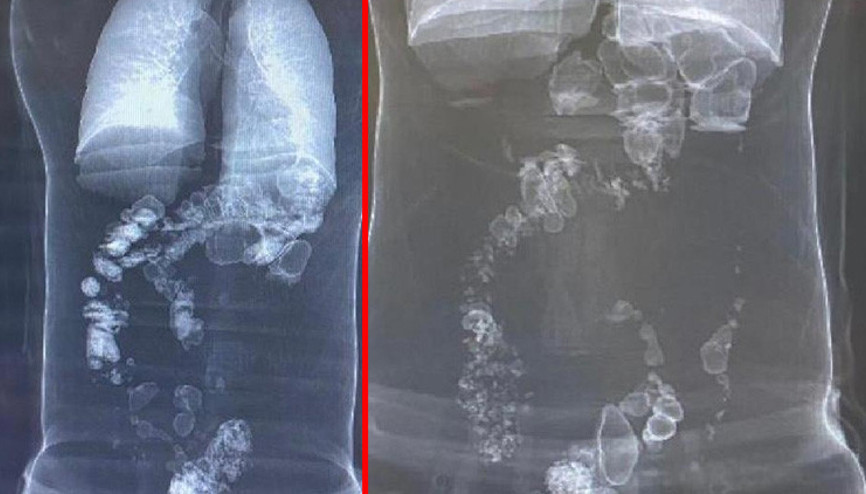

İstanbul’da yaşayan Mahmut ve İsmigül Nesim’in 4 çocuğundan biri olan 3 yaşındaki Berfin, mide ve bağırsaklarında 66 manyetik boncukla aylarca yaşadı. Bulantı ve kusma şikâyetiyle hastaneye kaldırılan minik kız, 5 saatlik kritik bir ameliyatla kurtarıldı. Çam ve Sakura Şehir Hastanesi Çocuk Cerrahi Kliniği’nden Opr. Dr. Mehmet Çakmak, minik Berfin'in vakasının şimdiye dek karşılaştıkları vakalar içinde rekor sayıda mıknatıs boncukla en şoke edici vaka olduğunu belirtti. Renkli mıknatısların küçük çocuklar için ölüm tuzağı olduğunu da vurgulayan Çakmak, "Her ay bu vakalarla karşılaşıyoruz, bu sözde oyuncakların satışı acilen yasaklanmalı" dedi.

#Mıknatıs Boncukİstanbul’da yaşayan Mahmut ve İsmigül Nesim’in 4 çocuğundan biri olan 3 yaşındaki Berfin, mide ve bağırsaklarında 66 manyetik boncukla aylarca yaşadı. Bulantı ve kusma şikâyetiyle hastaneye kaldırılan minik kız, 5 saatlik kritik bir ameliyatla kurtarıldı. Çam ve Sakura Şehir Hastanesi Çocuk Cerrahi Kliniği’nden Opr. Dr. Mehmet Çakmak, minik Berfin'in vakasının şimdiye dek karşılaştıkları vakalar içinde rekor sayıda mıknatıs boncukla en şoke edici vaka olduğunu belirtti. Renkli mıknatısların küçük çocuklar için ölüm tuzağı olduğunu da vurgulayan Çakmak, "Her ay bu vakalarla karşılaşıyoruz, bu sözde oyuncakların satışı acilen yasaklanmalı" dedi.